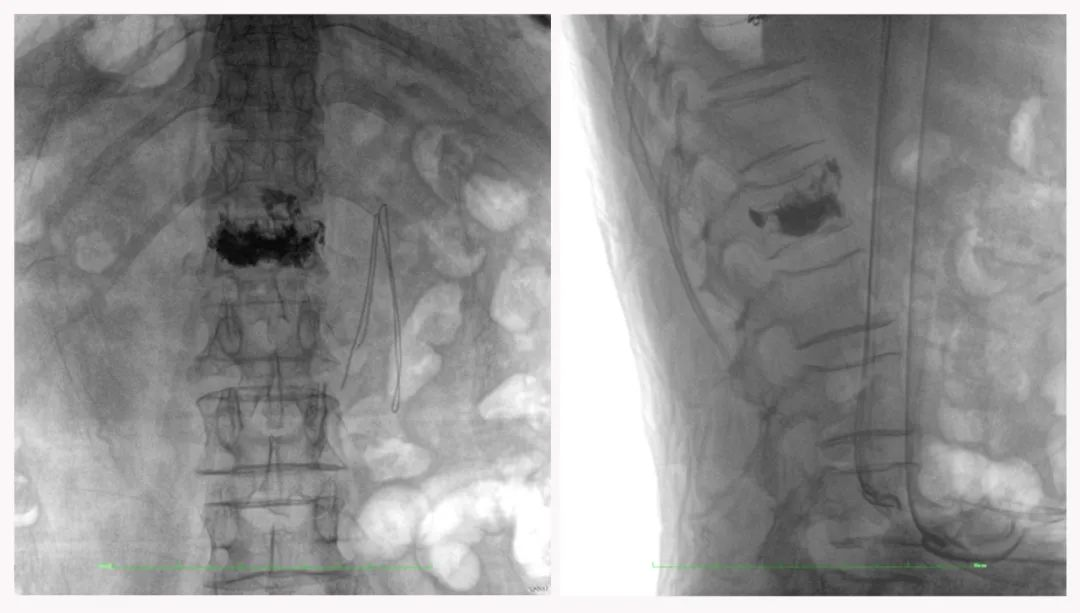

病例3:超聲支氣管鏡下肺活檢(80歲)

三維C形臂還可以創(chuàng)新性地應(yīng)用在呼吸介入領(lǐng)域。例如,在經(jīng)皮穿刺或經(jīng)支氣管鏡肺結(jié)節(jié)活檢、定位、消融等場景中,用于確認(rèn)工具是否到達病灶、消融范圍是否完全覆蓋病灶等。

二維影像無法準(zhǔn)確判斷工具是否到達病灶

三維各切面影像都顯示工具達到病灶內(nèi)